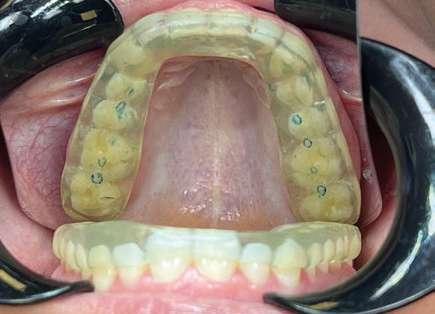

Fase 1: disyunción con MARPE

Tras colocar la anestesia palatina infiltrativa, el disyuntor osteo-soportado con tornillo hexagonal, se fijó de forma segura mediante los mini-tornillos utilizando un contra-ángulo de baja velocidad. Ese mismo día, se inició la expansión con pauta de 1 vuelta al día (0,16 mm por vuelta). Tras 43 días, se apreció la apertura de diastema inter-incisal y se continuó dando vueltas durante 18 días más hasta conseguir la corrección de la mordida cruzada posterior (Ilustración 5).

El paciente fue instruido en la higiene del dispositivo para evitar inflamación gingival y se realizaron controles rutinarios cada dos semanas. Al finalizar el procedimiento de expansión, el paciente fue monitoreado durante 75 días.

Evidencia clínica y radiográfica de la expansión:

 Separación visible de incisivos centrales, indicativa de apertura de la sutura palatina.

 Expansión confirmada mediante superposición de los modelos maxilares digitales previos y posteriores al tratamiento mediante MARPE (Ilustración 6). Se obtuvo un aumento transversal del 5,14 mm a nivel de los primeros molares.

Fase 2: corrección con alineadores Una vez corregida la discrepancia transversal y finalizado el periodo de control, el tratamiento continuó con alineadores Spark™, con un protocolo de uso de 22 horas diarias y cambios de alineadores cada 10 días. El tratamiento con alineadores se planificó en 2 etapas. Una primera etapa para abordar el plano vertical y una etapa final para abordar el plano sagital.